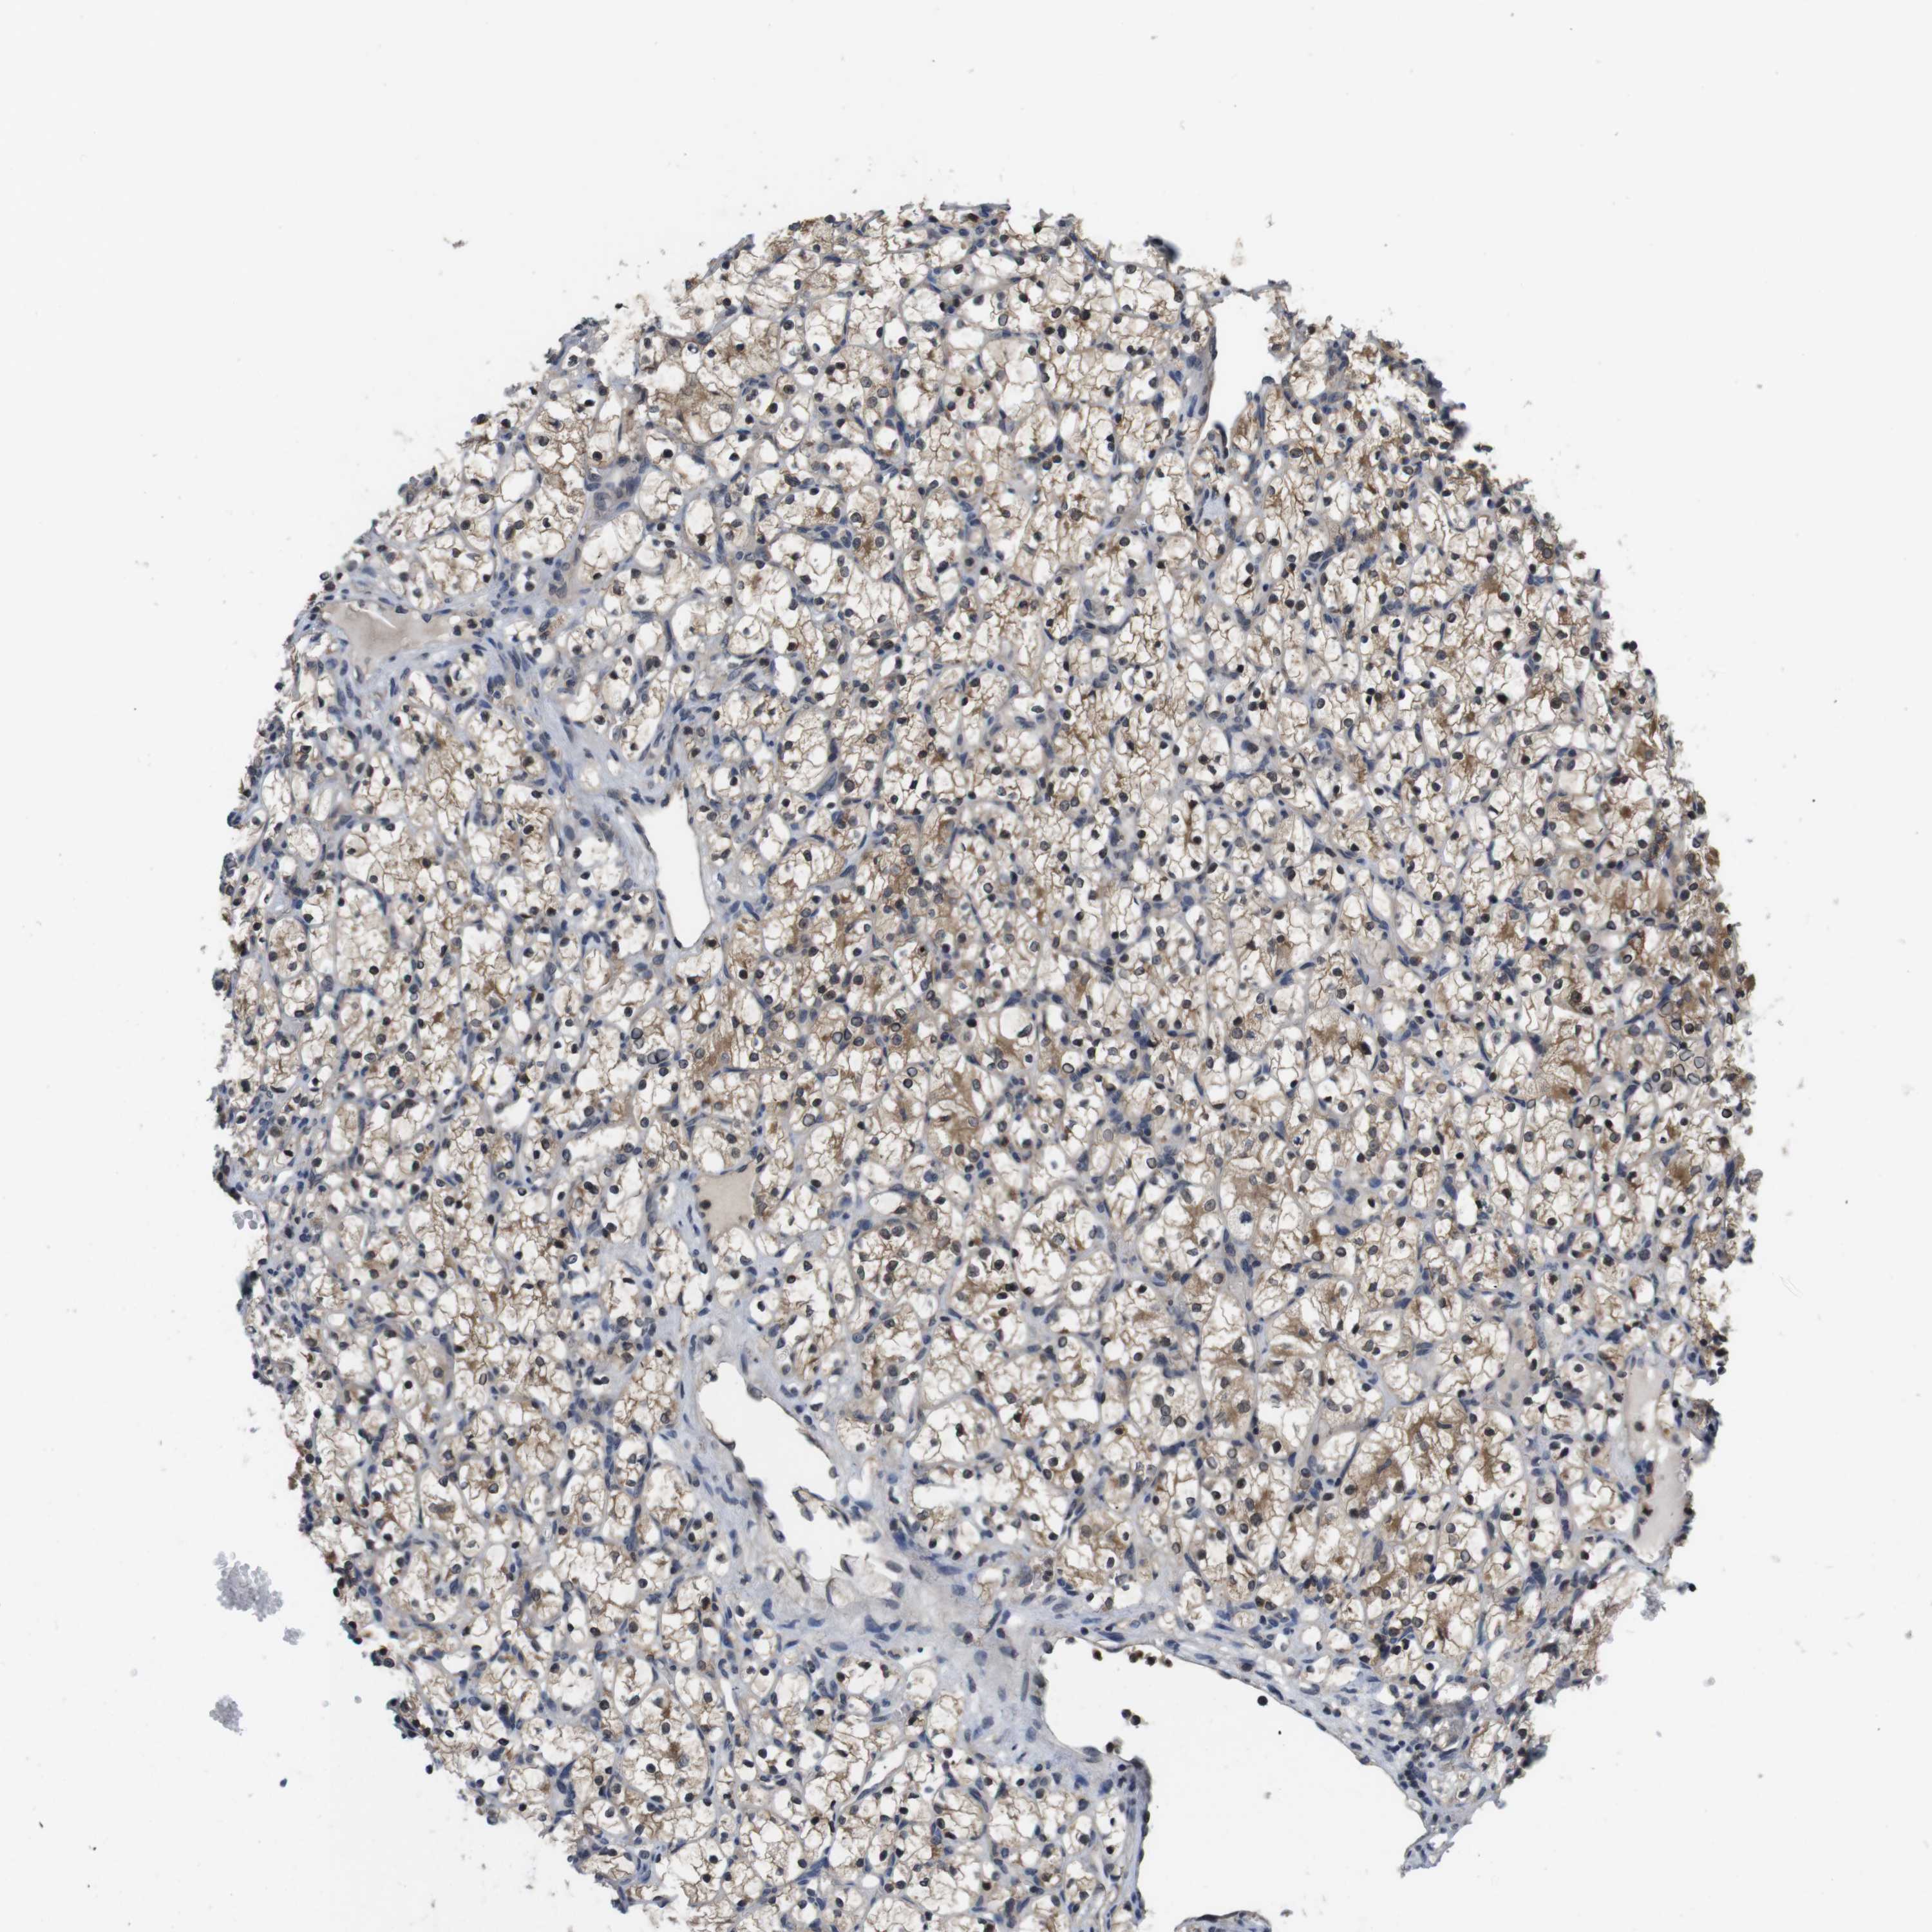

KIDNEY RENAL CLEAR CELL CARCINOMA (TCGA) - Interactive survival scatter ploti

The Survival Scatter plot shows the clinical status (i.e. dead or alive) for all individuals in the patient cohort, based on the same data that underlies the corresponding Kaplan-Meier plots. Patients that are alive at last time for follow-up are shown in blue and patients who have died during the study are shown in red.

The x-axis shows the expression levels (FPKM) of the investigated gene in the tumor tissue at the time of diagnosis. The y-axis shows the follow-up time after diagnosis (years). Both axes are complimented with kernel density curves demonstrating the data density over the axes. The top density plot shows the expression levels (FPKM) distribution among dead (red) and alive patients (blue). The right density plot shows the data density of the survived years of dead patients with high and low expression levels respectively, stratified using the cutoff indicated by the vertical dashed line through the Survival Scatter plot. This cutoff is automatically defined based on the FPKM cutoff that minimizes the p-score. The cutoff can be changed by dragging the vertical line or by entering a cutoff value in the square labeled "Current cut-off".

Under the Survival Scatter plot the p-score landscape (black curve; left axis) is shown together with dead median separation (red curve; right axis). Dead median separation is the difference in median mRNA expression between patients who have died with high and low expression, respectively. It is calculated as follows: median FPKM expression of dead patients with high expression - median FPKM expression of dead patients with low expression. This is intended to aid the user in visually exploring custom cutoffs and the associated p-scores and dead median separation.

Individual patient data is displayed and can be filtered by clicking on one or more of the category buttons on the top of the page. Categories describing expression level and patient information include: high, low, alive, dead, female, male and tumor stages. The scale of the x-axis can be toggled between linear and log-scale by clicking on the "x log" button. Mouse-over function shows TCGA ID, patient information and mRNA expression (FPKM) for each patient.

& Survival analysisi

Kaplan-Meier plots summarize results from analysis of correlation between mRNA expression level and patient survival. Patients were divided based on level of expression into one of the two groups "low" (under cut off) or "high" (over cut off). X-axis shows time for survival (years) and y-axis shows the probability of survival, where 1.0 corresponds to 100 percent.

FADD is potential prognostic, high expression is favorable in Kidney Renal Clear Cell Carcinoma (TCGA)

: 21.03

Average pTPM 23.7

Number of samples 521